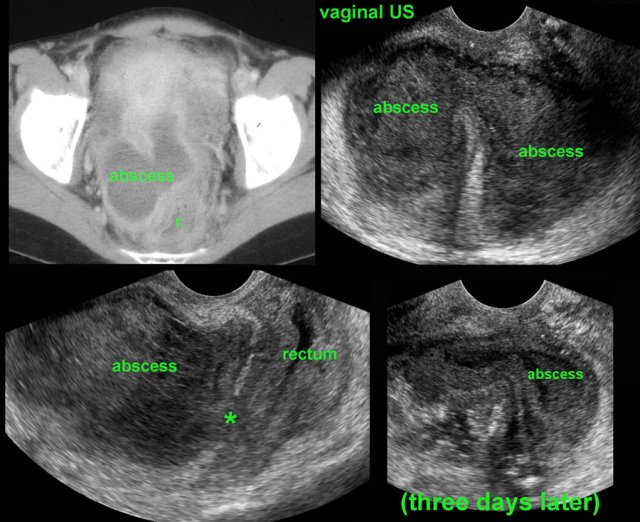

This 25 year old woman presented ten days after surgery for perforated appendicitis with fever.

She had a Douglas abscess, lying close to the rectum (r.) showing a thickened wall.

Vaginal US confirmed the abscess and secondary rectal wall thickening.

At the spot of closest contact (*) the wall layers of the rectum were locally obliterated.

Follow-up vaginal US showed complete, spontaneous transrectal evacuation.